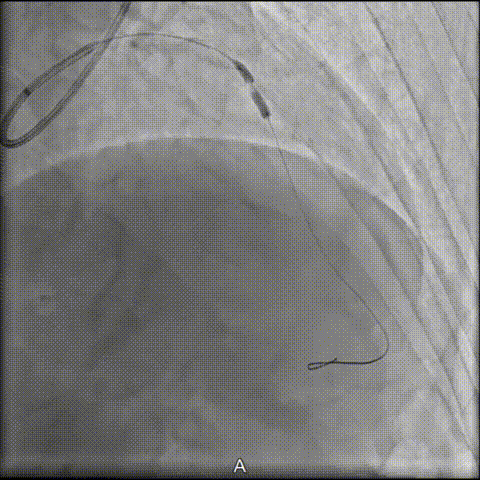

2 传统IVL球囊无法通过

接着,拟采用2.5×12mm 传统IVL球囊未能通过钙化病变段。

3 旋磨治疗失败并引发夹层

随后,启动旋磨策略:1.25mm磨头首次旋磨后嵌顿,造影提示夹层形成,遂结束旋磨。